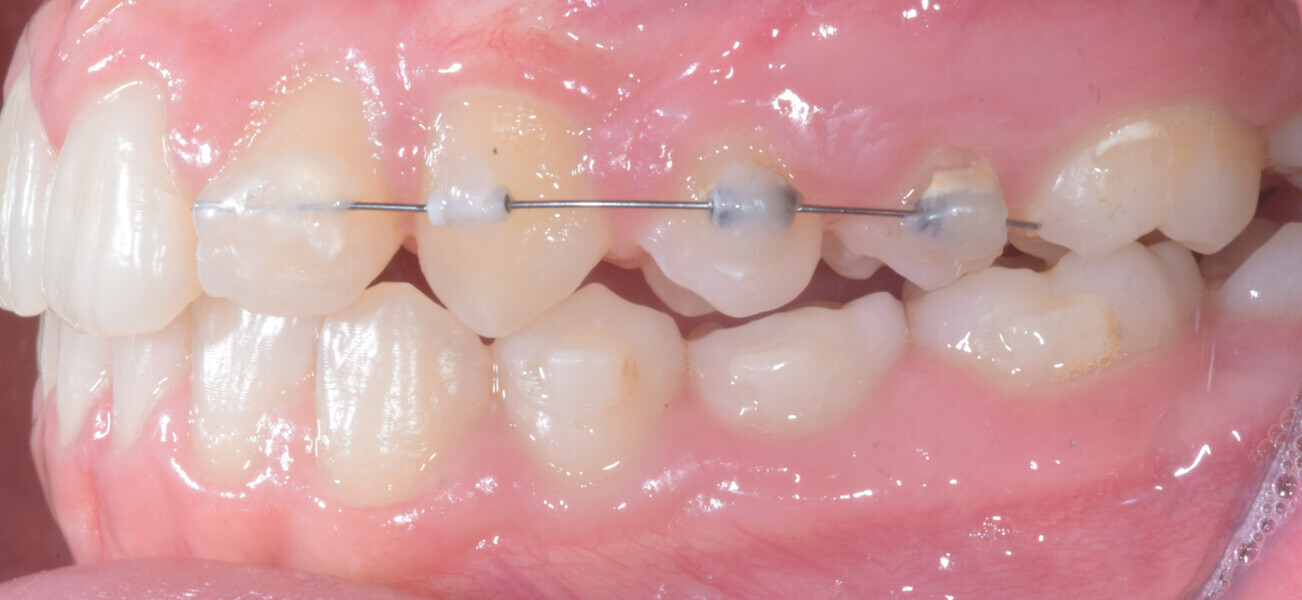

At the end of the first stage of aligner treatment (Figs. 20–24), the auxiliary phase began with the bonding of two MTAs on the maxillary right premolars. A 0.016-in Australian archwire, shaped into a cantilever configuration, was then inserted into the MTAs, and a cutout was created on the final aligner. To prevent rotation, the archwire was cinched distal to tooth #15 and the cinch covered with composite.

At the same time, the impacted canine was exposed by laser, a button was bonded on to it and the cantilever was connected to the button using an elastomeric thread. The final aligner was used for space maintenance while the cantilever was reactivated until the canine had erupted (Figs. 25–27). After complete eruption, further MTAs were bonded on the canine and on the lateral incisor, and a 0.014 in. NiTi archwire was used to finalise the eruption (Figs. 28–30). Only at the end of the forced eruption phase did the further aligner stage take place, aimed at achieving an ideal Class I relationship on the right by maxillary right mesialisation using Class III elastics and 27 maxillary aligners and 13 mandibular aligners (Figs. 31–33).